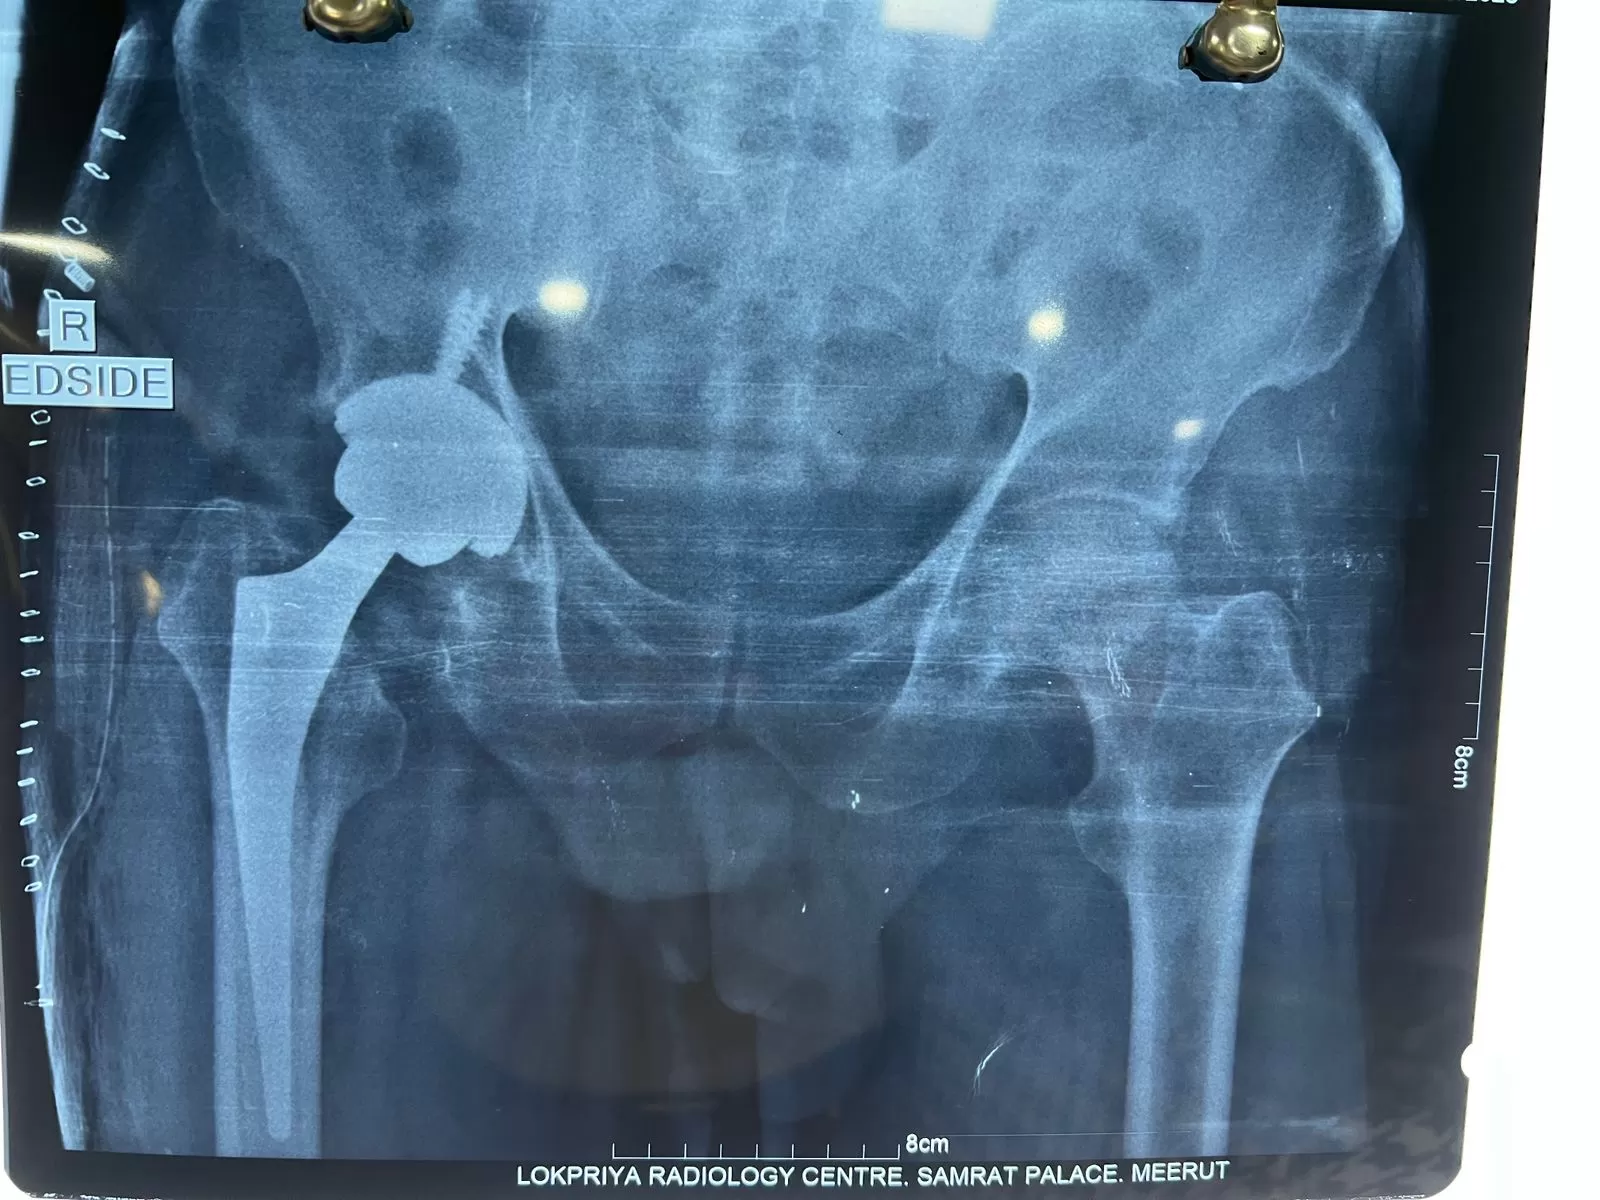

Mr. Neeraj Tyagi

Name: Mr. Neeraj Tyagi

Date of Operation: 30 September

Age: 48 Years